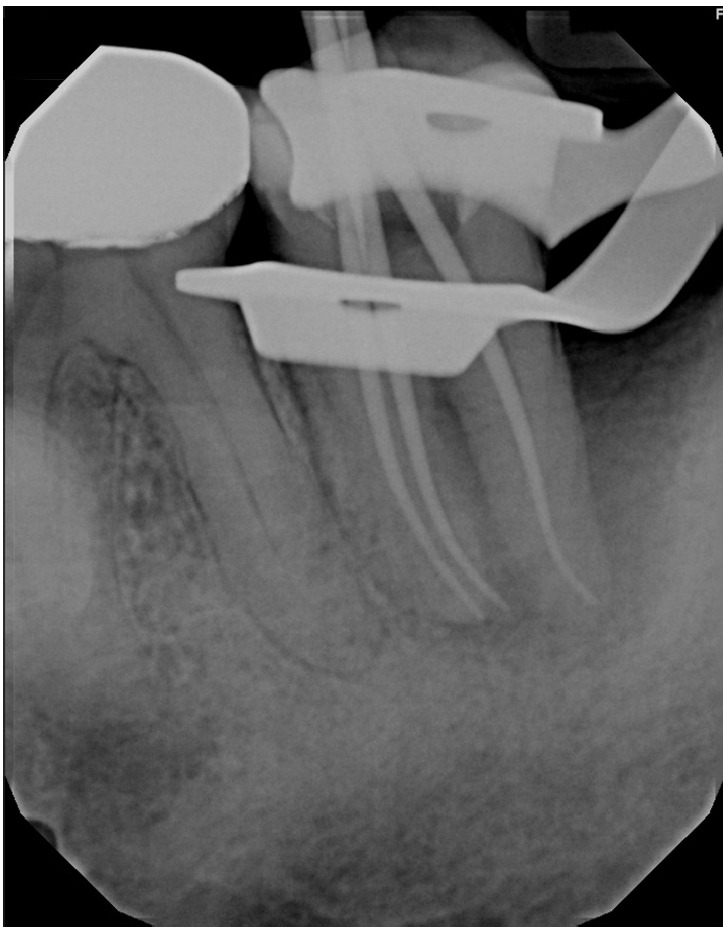

牙髓-牙周病变并发牙髓撕裂是一个诊断和治疗上的挑战。本病例报告描述了一位66岁男性下颌第二磨牙患者(#18)的成功治疗,该患者表现为EPL合并骨水泥撕裂。临床检查显示窦道引流,牙周深袋,x线表现为“j形”病变和不透射线的骨水泥碎片。该牙齿曾接受过牙髓治疗。多学科的方法包括牙髓治疗和手术切除骨水泥撕裂。在24个月的随访中,临床和影像学检查显示牙周健康、骨再生和病变消退有显著改善。本病例强调了在鉴别诊断epl时考虑骨水泥撕裂的重要性,并证明了牙髓-牙周联合入路对实现可预测结果的有效性。

Endodontic-periodontal lesions (EPLs) complicated by cemental tears present a diagnostic and therapeutic challenge. This case report describes the successful management of a 66-year-old male patient with a mandibular second molar (#18) exhibiting an EPL complicated by a cemental tear. Clinical examination revealed a draining sinus tract, deep periodontal pockets, and radiographic evidence of a "J-shaped" lesion and a radiopaque cemental fragment. The tooth had previously initiated endodontic treatment. A multidisciplinary approach involving endodontic treatment and surgical removal of the cemental tear was implemented. At 24-month follow-up, clinical and radiographic examination revealed significant improvement in periodontal health, bone regeneration, and resolution of the lesion. This case highlights the importance of considering cemental tears in the differential diagnosis of EPLs and demonstrates the efficacy of a combined endodontic-periodontal approach for achieving predictable outcomes.